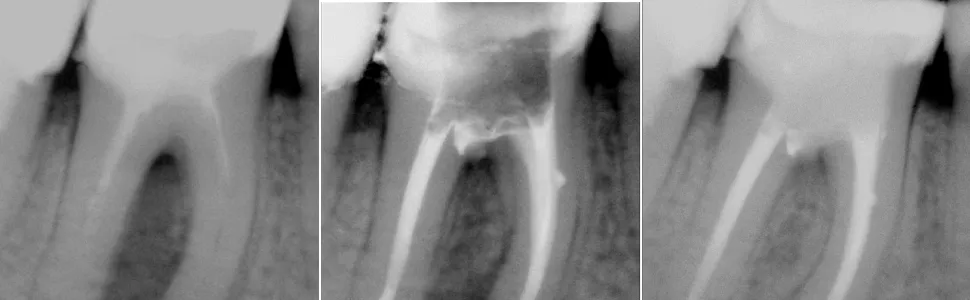

Rola zdjęcia RTG: co widać na standardowym prześwietleniu?

Standardowe zdjęcie RTG punktowe jest często pierwszym krokiem w diagnostyce. Pozwala ono uwidocznić miejsce perforacji, zwłaszcza jeśli jest ona większa i towarzyszy jej stan zapalny w kości. Na zdjęciu możemy zobaczyć ubytek w strukturze zęba lub rozjaśnienie w kości wokół korzenia, świadczące o procesie zapalnym. Należy jednak pamiętać, że zdjęcie dwuwymiarowe może nie zawsze pokazać pełny obraz, zwłaszcza w przypadku małych perforacji lub tych zlokalizowanych w skomplikowanych obszarach.

Tomografia CBCT: dlaczego trójwymiarowy obraz jest złotym standardem w diagnostyce?

Współczesna stomatologia oferuje znacznie precyzyjniejsze narzędzia. Tomografia komputerowa wiązki stożkowej (CBCT) jest obecnie uważana za złoty standard w diagnostyce perforacji. Dzięki niej uzyskujemy trójwymiarowy obraz struktur zęba i otaczającej kości. Pozwala to na bardzo dokładną ocenę lokalizacji, rozmiaru i kształtu uszkodzenia, a także na ocenę stanu kości wokół perforacji. CBCT daje mi możliwość precyzyjnego zaplanowania leczenia, co znacząco zwiększa jego skuteczność.

Mikroskop endodontyczny: jak precyzyjne powiększenie pomaga zlokalizować problem

Mikroskop zabiegowy to moje "trzecie oko" w gabinecie. Umożliwia on bezpośrednie uwidocznienie miejsca perforacji wewnątrz zęba, często niewidocznej gołym okiem. Dzięki powiększeniu od kilku do nawet kilkudziesięciu razy oraz silnemu oświetleniu, mogę dokładnie ocenić perforację, usunąć ewentualne zanieczyszczenia i precyzyjnie zaaplikować materiał uszczelniający. Mikroskop jest nieoceniony nie tylko w leczeniu, ale i w samej diagnostyce, pozwalając mi zobaczyć problem z najwyższą dokładnością.